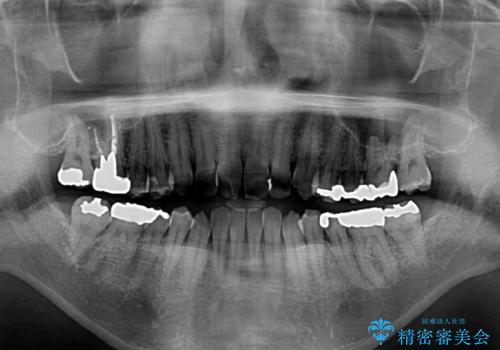

通常の咬み合わせ位置と比較して、上顎の歯列が全体的に前方にある状態で、上下前歯の前後方向の位置に著しい差がありました。

上顎奥歯付近にアンカースクリューを用い、上顎歯列全体の後方移動と、大臼歯圧下を促し、前歯の上下関係を改善することとしました。

奥歯には目立つ銀歯が多くあるので、矯正治療後には下顎の銀歯をセラミッククラウンやセラミックインレーにより、補綴・修復治療することとしました。